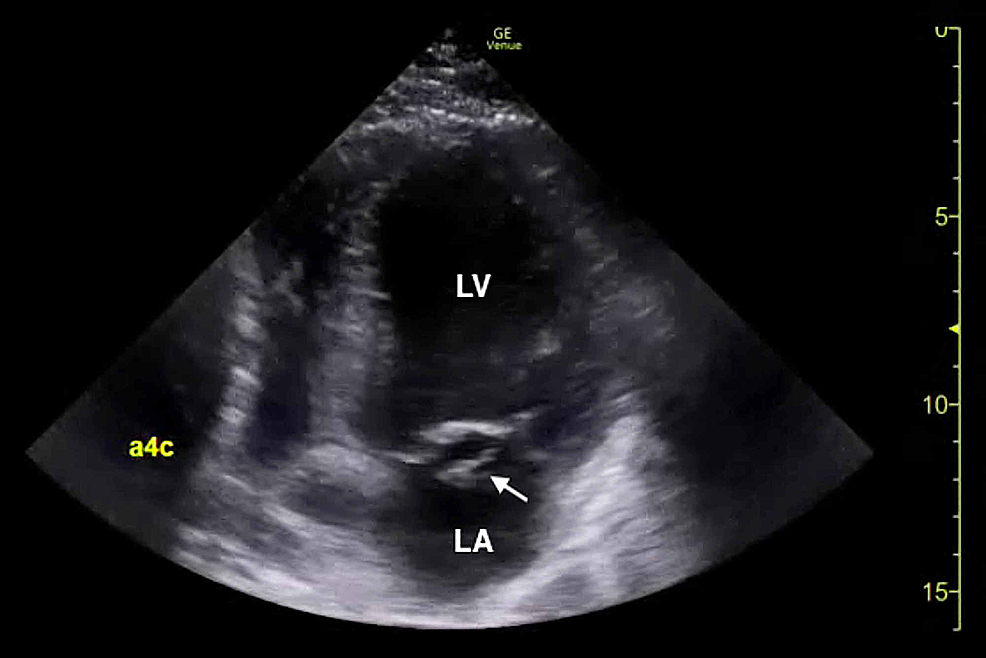

The clinical history was also concerning for an undiagnosed cardiomyopathy, particularly given the heart murmur appreciated on examination and his stated history of MVP for which the patient had never sought outpatient cardiology follow-up. Bedside LUS and FOCUS were then performed by emergency medicine resident physicians. LUS was notable for the presence of a diffuse B-line profile consistent with pulmonary edema (Figure 1). FOCUS was unremarkable for evidence of pericardial effusion, signs of right heart strain, or decreased LV contractility. However, FOCUS revealed a dilated left atrium (LA) and a suspected posterior FML, with the posterior MV leaflet seen protruding into the LA (Figures 2, 3; Videos 1, 2).

The constellation of FOCUS findings immediately prompted a formal comprehensive transthoracic echocardiogram (TTE) and emergent cardiology and cardiothoracic surgery consultations. TTE confirmed preserved LV systolic function, LA dilation, and flail motion of the posterior MV leaflet with severe eccentric MR (Figures 4, 5; Videos 3-5).

The patient was admitted to the cardiovascular intensive care unit (CVICU) for transesophageal echocardiogram (TEE), cardiac catheterization, and cardiothoracic surgery consultation. TEE demonstrated preserved LV systolic function, severe flail motion of the posterior mitral leaflet, and severe MR (Figure 6; Video 6). Cardiac catheterization was performed and demonstrated angiographically normal coronary arteries. Cardiothoracic surgery performed MV repair with resection of the flail P2 segment and MV annuloplasty. The patient was ultimately discharged on hospital day 9 after a stable and uneventful postoperative course.